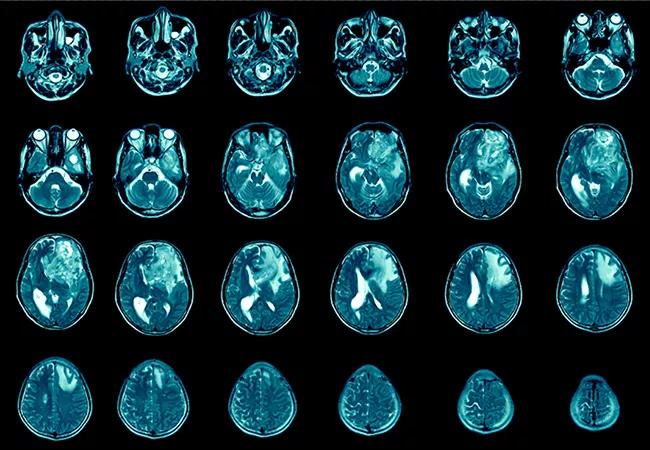

High-Fat Diet Linked to Aggressive Glioblastoma in Preclinical Study

A high-fat diet accelerates and intensifies glioblastoma in preclinical models, according to a recent study by Cleveland Clinic researchers published in the Journal of Clinical Investigation (2021;131[17]:e138276). The findings highlight the need for more research into the possible utility of dietary interventions to reduce the risk and severity of glioblastoma in humans.